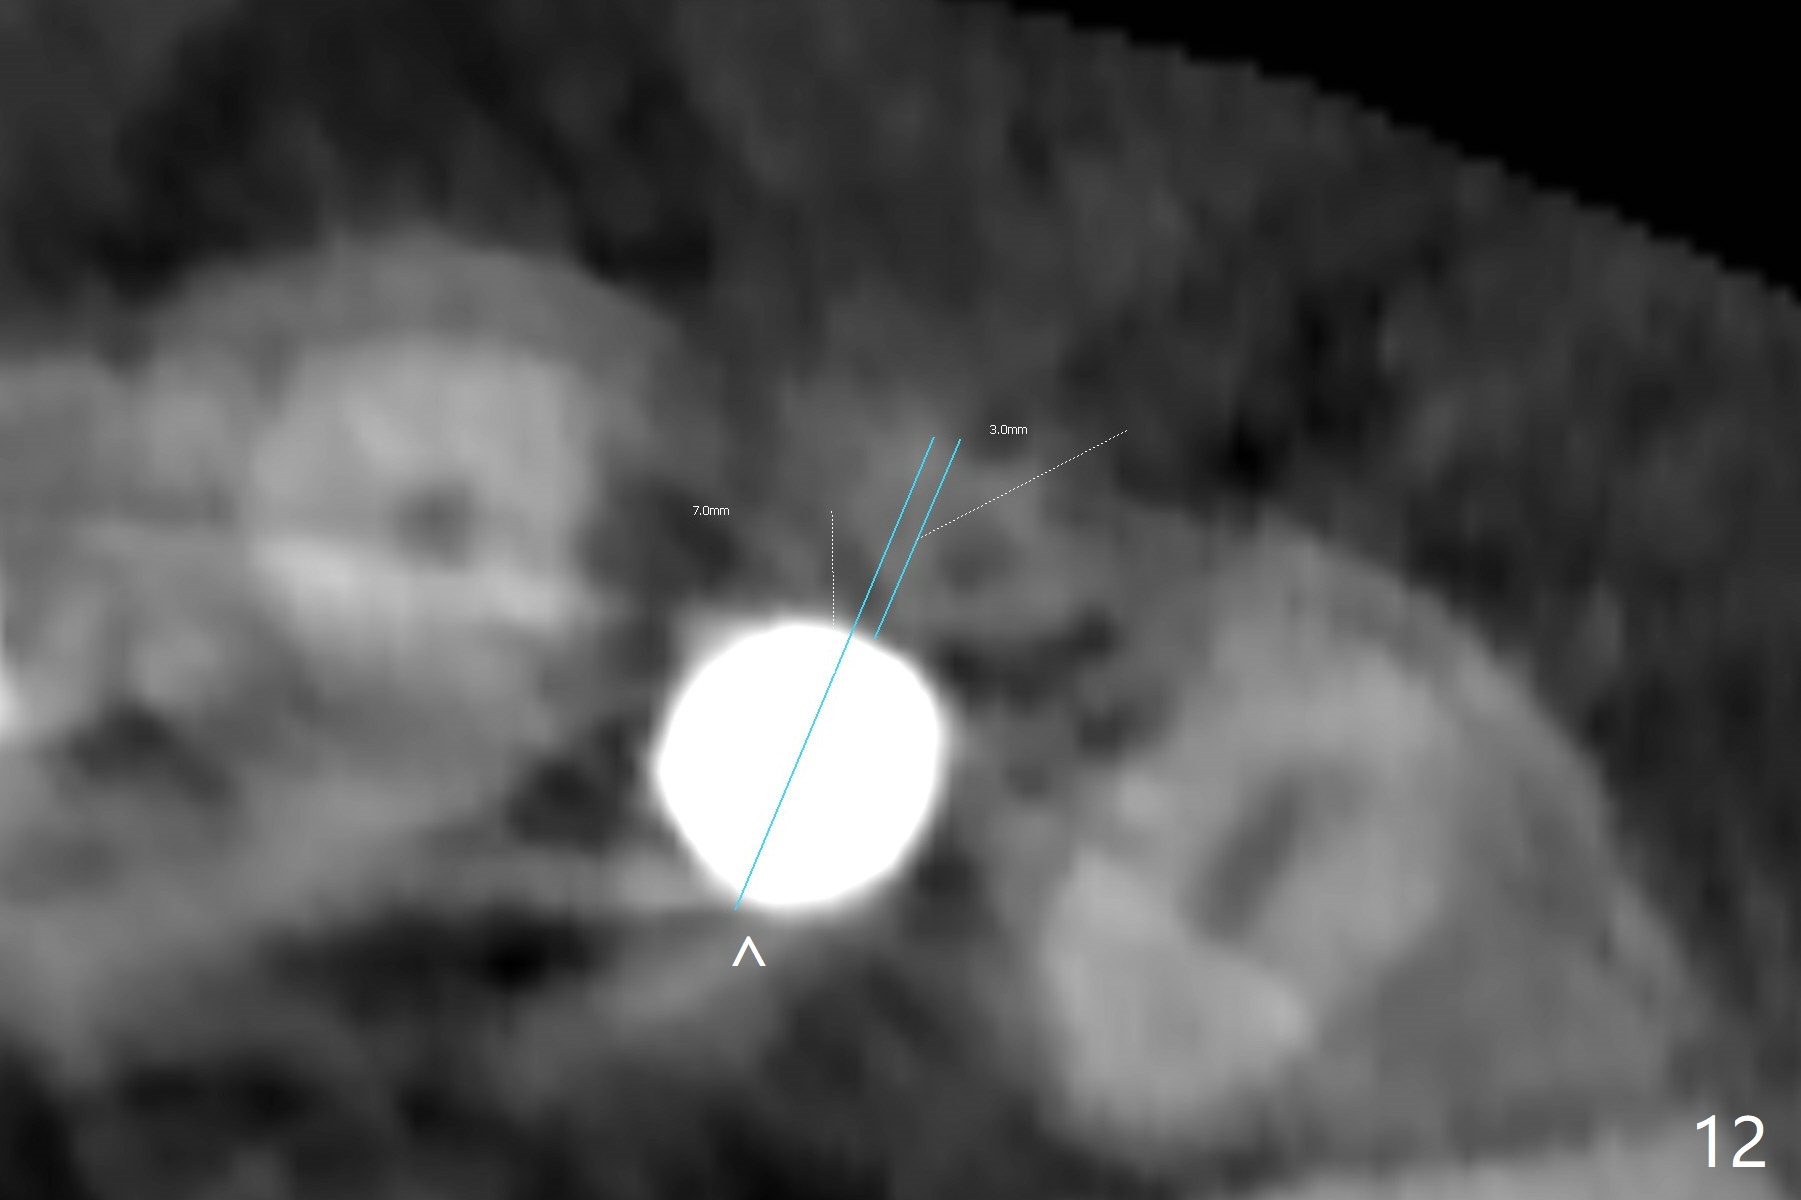

When the patient returns, the crown at #10 has displaced incisally (Fig.1,2 arrow). The initial depth is 15 mm (Fig.3, palatal gingival margin). After a 3.8x12 mm SM implant is placed (Fig.4), allograft is packed in the peri-implant space (*, as compared to Fig.3) and a 3.9x4(3) mm abutment is placed (A). More allograft is placed in the peri-abutment space (Fig.6 *). The existing crown (Fig.4,5 C) is hollowed, relined (R) and used as an immediate provisional (Fig.7-9). The patient is pleased with the appearance of the apically-repositioned provisional (Fig.7 arrow). She returns for impression 3.5 months postop (Fig.10). After change of abutment to 3.9x4(4.5) mm and new provisional, impression is retaken 5 months postop (Fig.11,12). It appears that the implant is palatally placed and a little large for the site (Fig.11 (B: buccal); Fig.12 (^: thin layer of the palatal plate)). If an angled abutment were used, a screw-retained crown might have been feasible. Due to the new provisional, the gingiva looks healthy when a permanent crown is cemented (Fig.13).